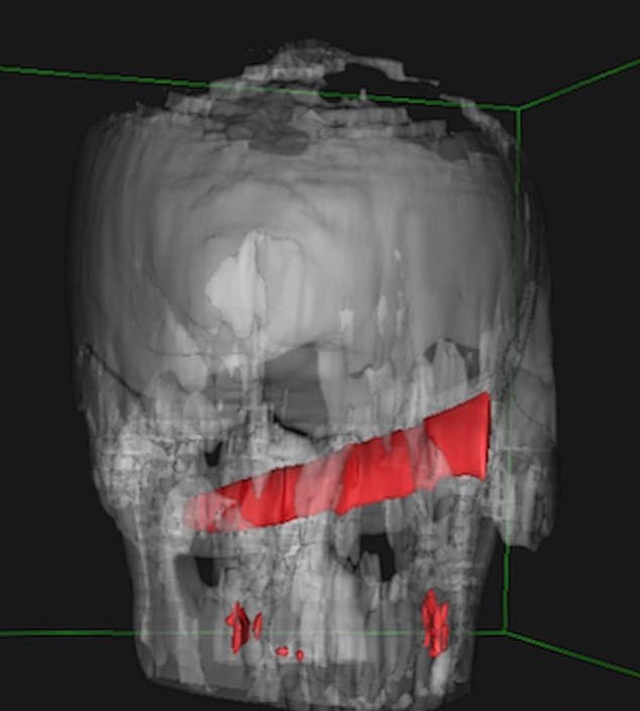

Операция состоялась только на четвертый день после происшествия. В ней принимали участие офтальмологи, отоларингологи, челюстно-лицевые хирурги и нейрохирурги. Врачи смогли без повреждений извлечь нож и головы пациента, но затем им пришлось временно зашить ему глаз. На данный момент жизни парня ничего не угрожает.